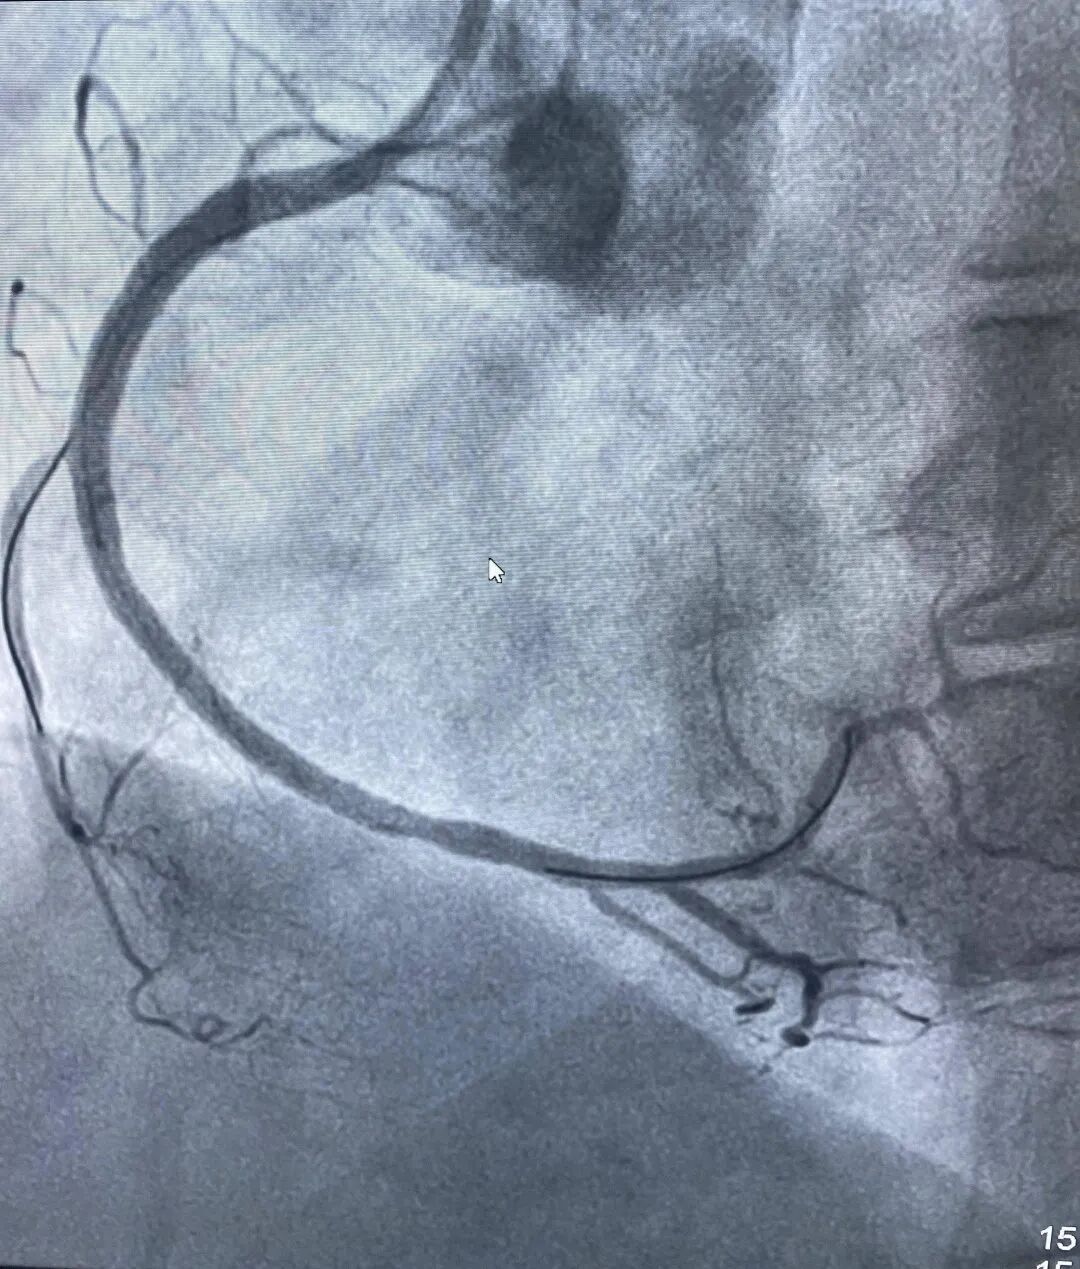

情况紧急,胸痛中心迅速响应,在与家属沟通并签署知情同意书的同时,同步办理住院手续,全程开通绿色通道,最快的速度把吕女士送入导管室接受急诊PCI治疗(经皮冠状动脉介入治疗)。在王宁夫主任医师指导下,徐鹏和钱宇峰副主任医师为她进行介入治疗,术中发现她的右侧冠状动脉近段完全闭塞,通过球囊扩张并植入支架,成功开通了堵塞的血管,恢复了心肌供血。

术后右冠完全开通